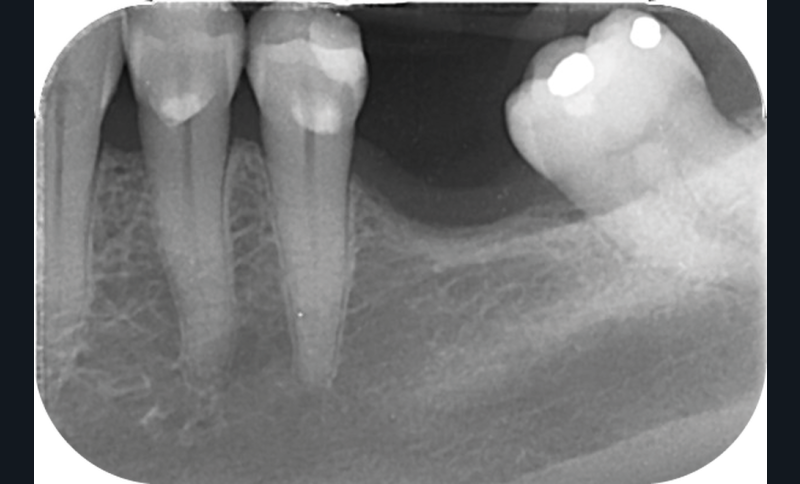

Cette version, quand elle se produit, modifie les espaces interdentaires et complique l’hygiène proximale des patients. Des caries peuvent alors se développer en interproximal sans que cela soit forcément visible à l’examen visuel (fig. 3 et 4). Les radios de type bite-wing (rétro-coronaires) prennent alors tout leur sens (fig. 5 et 6).